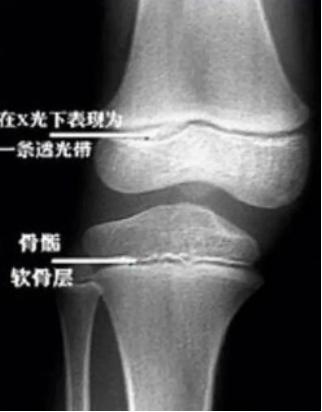

几乎没有产品会对增高有用,尤其是对成年人,因为骨骺线闭合之后,骨骼不会再增长,长高的空间也消失了。虽然对于想要再长高的人群来说,这是一个残酷的结论,但是这就是事实。人在青春期时,身高的增长非常快。长高的原因主要是骨骼发育中表现的长度增长。孩子能不能长高,与骨骼的生长发育潜力有非常密切的关系,而骨骺线就是一个非常重要的标志。骨头增长就像是盖摩天大楼,在盖之前需要有足够高度的脚手架才能搭建大楼的主体结构。其中,软骨基质就是骨骼生长的“脚手架”,通过脚手架,工人们(成骨细胞)带着原料(蛋白、矿物质等)顺着楼梯(血管)一级级往上建造着高楼。软骨细胞不断增生同时又被不断骨化,使得骨的长度不断地增加。这个工程会一直进行到成年期的初期(约18岁),摩天大楼的建造也就接近了尾声,脚手架需要慢慢地清空,楼梯也会一级级回收,盖楼的速度也会越来越慢。回到微观骨骼上来看,这时候骨骺板(富含有血管的软骨生长板)会被骨组织取代,成为残余下来的骨骺线,骨干也就停止增长了。

骨干和骨骺的间隔成了一条线,两部分骨「合并」到了一起,骨骺线闭合,长高的空间也消失了。由于女性的骨骺闭合一般比男性早,所以成年女性比男性矮。网友们纷纷表示对自己成年后长高无望的失落。